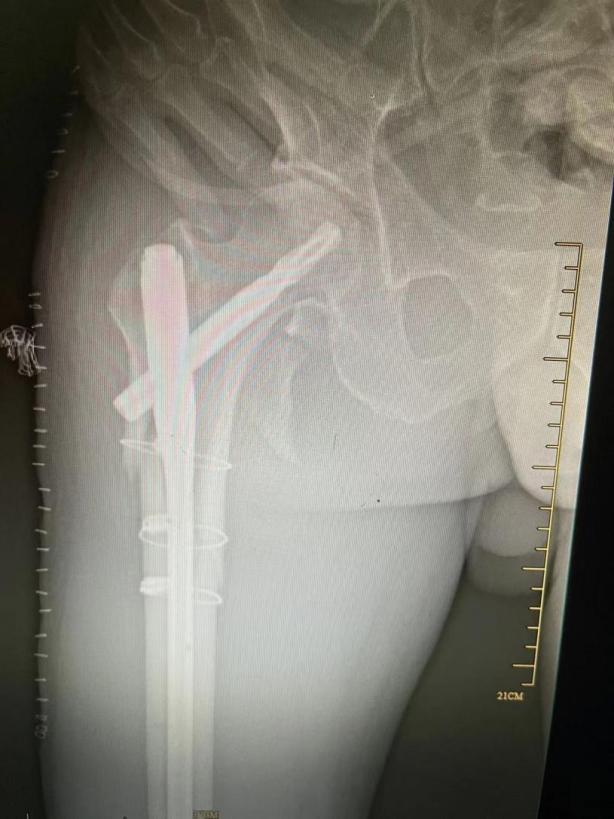

髖部骨折主要是股骨粗隆間骨折和股骨頸骨折,臺(tái)州市中醫(yī)院骨傷科研究室守正創(chuàng)新,針對(duì)老年髖部骨折,采取中西醫(yī)結(jié)合的方法,在中醫(yī)藥補(bǔ)益氣血、活血化瘀等基礎(chǔ)上,可予以閉合復(fù)位內(nèi)固定手術(shù)和人工股骨頭置換手術(shù),取得良好的療效。